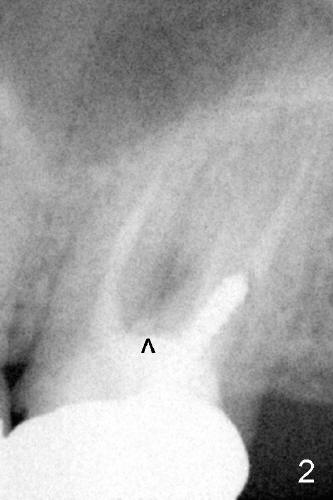

A 42-year-old lady has had problems with the tooth #15 for 4 years. First the crown was dislodged with open margin and furcal lesion (> in Fig.1, P: post; X-ray taken in 2008). Since 2009 (Fig.2,3), the tooth has occasional swelling. The furcal radiolucency remained in the panoramic X-ray (Fig.4 and 4'). Now the patient agrees to have extraction and implant placement.

Preliminary treatment plan is antibiotic to control acute infection, atraumatic extraction, bone expansion of the septum, possible sinus lift and immediate implant placement (diameter 7 or 8 mm, see Fig.3 for socket dimensions).